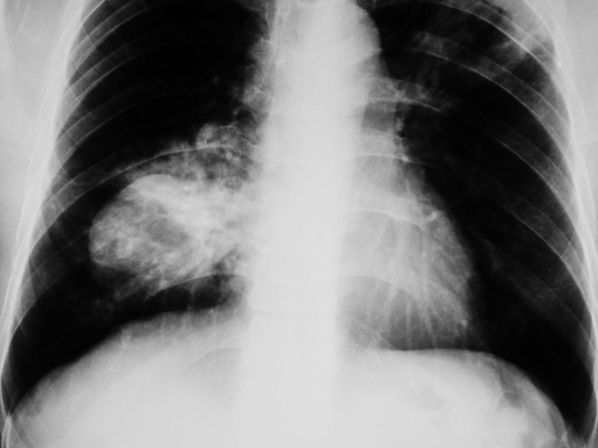

La doctora Dolores Isla, presidenta de ICAPEM y jefa de Oncología Médica en el Hospital Lozano Blesa, ha destacado la necesidad de mejorar la detección temprana del cáncer de pulmón en mujeres. Este llamamiento se realizó durante un evento coorganizado por ICAPEM y la Asociación Española de Afectados por Cáncer de Pulmón (AEACaP), con apoyo de la Fundación PharmaMar.

“El cáncer de pulmón de célula pequeña sigue siendo uno de los grandes retos clínicos. En el caso de las mujeres, su abordaje requiere un análisis más profundo, ya que pueden existir diferencias en sus factores de riesgo, características clínicas, evolución y respuesta a los tratamientos”, apuntó la doctora Isla.

El cáncer de pulmón de célula pequeña en mujeres, que representa el 15% de los diagnósticos de este tipo de cáncer, es especialmente agresivo y ha visto un incremento en su incidencia entre mujeres recientemente. Durante el evento, se aprobó un Manifiesto que destaca los principales desafíos para las mujeres con este diagnóstico y sugiere acciones específicas para mejorar su cuidado.